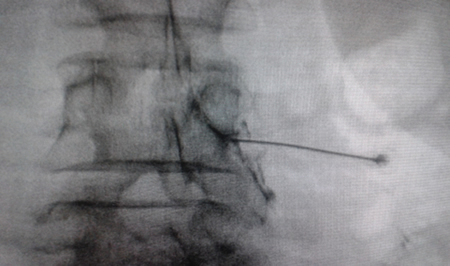

Access by transforaminal route is the most widely used (4). The patient is placed in prone position with an abdominal pillow to reverse physiological lordosis. The most commonly used RF needles or cannulas are 20 or 22 G diameter and 98 mm long with 0.5 or 1 cm active tip. Following asepsis with alcoholic chlorhexidine and placement of sterile fields, radiological approaches in anteroposterior, oblique and lateral incidence are performed. In anteroposterior incidence and moving the arc in cranio-caudal direction, the double arc of the lower vertebral edge is deleted. In oblique incidence between 20 and 30 degrees ipsilateral to the DRG to be treated, the classic image described as “Scotty Dog” will be displayed, which is the result of bringing the articular facets and the spinous process closer to the contralateral side. The entry point will then be immediately below the pedicle. After local anesthesia with 1 % lidocaine, the needle will be inserted following a tunnel vision and will not advance beyond half of the pedicle in this projection to prevent neural injury. In lateral projection, it will be inserted into the roof of the neuroforamen (Figures 1 and 2) but the final location will be determined by sensory-motor nerve stimulation. Sensory stimulation is to cause paresthesia or pain in the affected territory with stimulation between 0.3-0.6 v. During motor stimulation fasciculations can be caused in the affected territory with a voltage of twice that necessary to cause paresthesia. If an intraganglionar denervation, promulgated by some authors, is desired, both sensory and motor stimulation will be positive at less than 0.3 v. As this is a more painful procedure, it is advised to administer local anesthetics after the painful stimulus and before treatment. The impedance should be kept below 450 ohms, which is achieved by infusing saline before proceeding with RF (4). The use of contrast is good practice, as it rules out the intravascular and intrathecal position of the radiofrequency cannula.

Fig. 1. Lateral radiological view showing a radiofrequency cannula at the anterosuperior angle or roof of the neuroforamen, approximate topography of the dorsal root ganglion

Fig. 2. Anteroposterior radiological view of a radiofrequency cannula placed in neuroforamen L4-L5, in the so-called safety triangle, after contrast injection. A thickening of the radiculogram is observed at the roof of the neuroforamen, which may correspond to the dorsal root ganglion of L4